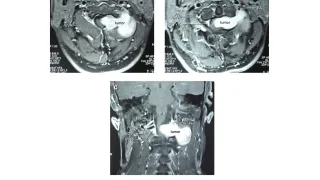

手術日+728日目 2026/2/25(水)(筋肉内神経鞘腫)